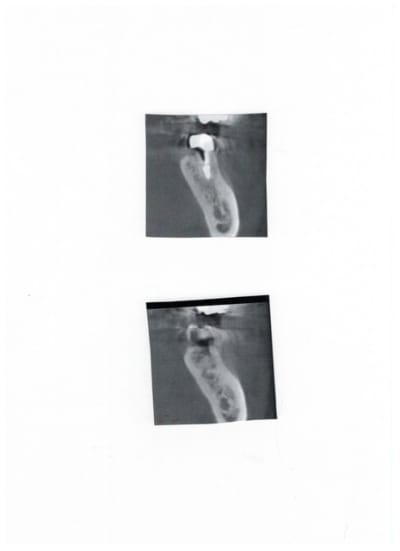

Voici un exemple de couplage microscope opératoire/cbct

RTE 36 en octobre2012 ;3 heures de RTE pour recherche de canaux sous micro inserts ultrasons/il y avait une LIPOE

digue+hypo+système R-endo microméga instruments à mains

vérification au CBCT en 2016

disparition des LIPOE

ici on obtient une guérison apicale